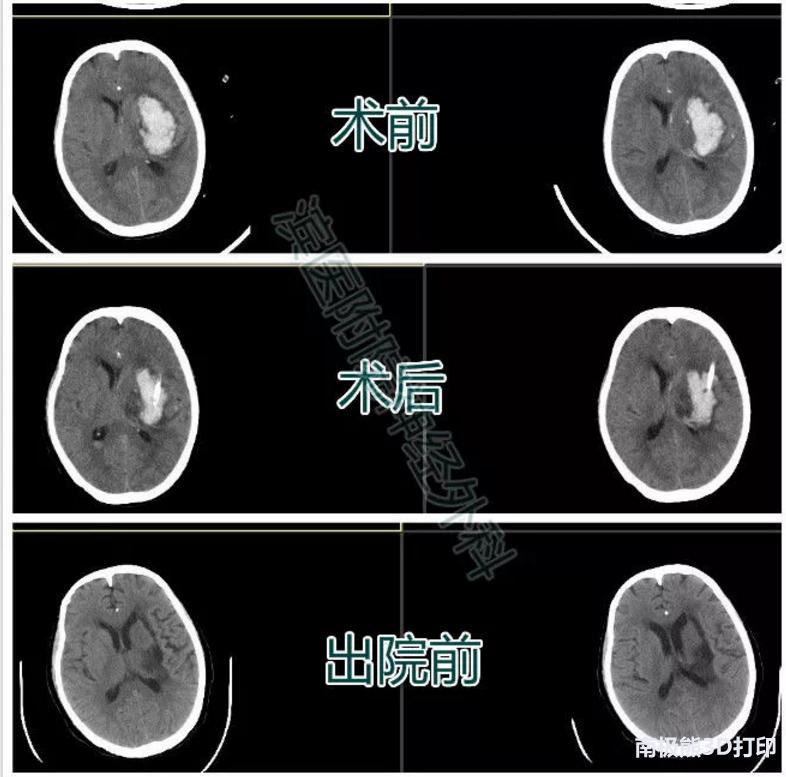

患者高某某,女,72岁,因“突发意识不清1小时”入院。

入院查体:昏迷状态,刺痛睁眼,无言语。双侧瞳孔直径约2mm,对光反应迟钝。右侧肢体刺痛无反应,左侧肢体刺痛屈曲。颅脑CT示左侧基底节区脑出血。入院后排除手术禁忌,行3D导板下经额部血肿腔穿刺术,术后复查颅脑CT如图,引流管位于血肿腔中心,穿刺位置满意。术后半月复查颅脑CT示血肿完全吸收,右下肢肌力3+,右上肢肌力3级。3月后患者门诊复查右侧肢体肌力恢复到4级,生活自理。

患者二影像资料